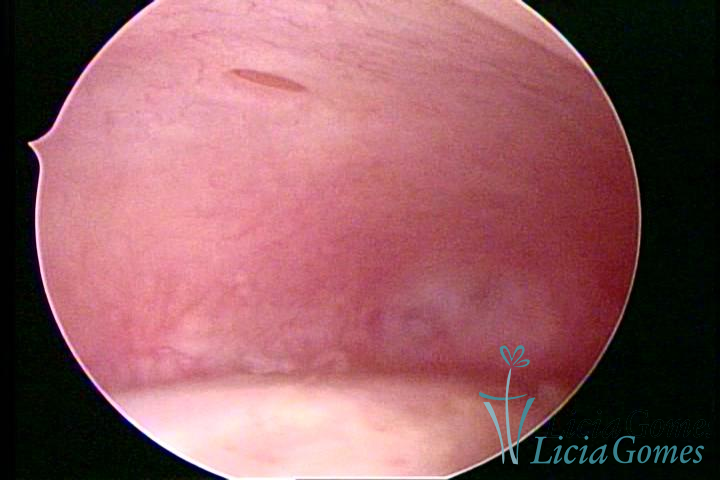

ADENOMIOSE

É a presença de tecido endometrial na camada muscular do útero

A vídeo-histeroscopia permite diagnosticar às lesões próximas às camadas miometriais superficiais, próximo ao endométrio visualizando lesões de coloração violácea, circunscritas, ou acastanhadas com conteúdo achocolatado.